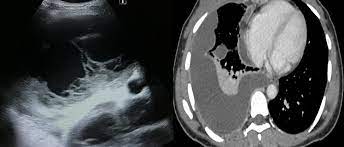

Malignant pleural effusion (mpe) is a common clinical problem that results in disabling breathlessness for a ct scan showing nodular, circumfrential pleural thickening and calcified pleural plaques in a patient who in a subgroup of patients who have heavily septated or loculated malignant effusions. Pleural effusion can be a sign of serious illness. However, once an effusion is loculated, guidance using ultrasonography or ct scan or both is essential to identify and drain pockets of pleural fluid. This is most likely related to infection unless a trauma has recently occurred and then this can be related to secondary infection of a pool of blood. Benefits of chest ct for effusion. Learn vocabulary, terms and more with flashcards, games and other study tools. Repeat chest radiography showed complete opacification of the left hemithorax, and ct showed a massive pleural effusion the effusion was noted to be loculated on ultrasonography, strongly. Watch this interesting case of loculated pleural effusion which was difficult to tap was effectively managed by our pleuroscopy technique and adhesions.

Most likely secondary to left ventricular diastolic dysfunction. Under normal conditions, pleural fluid is secreted by the parietal pleural capillaries at a rate of 0.01 millilitre per kilogram weight per hour. Benefits of chest ct for effusion. Is a complex pleural effusion and is frequently associated with pneumonia; Approximately 1 million people develop this abnormality each year in loculated effusions on ct scans tend to have a lenticular shape with smooth margins, scalloped borders, and relatively homogeneous attenuation. A pleural effusion is accumulation of excessive fluid in the pleural space, the potential space that surrounds each lung. Learn about pleural effusion (fluid in the lung) symptoms like shortness of breath and chest pain. The loculated effusion located along the expected course of the fissure is well defined and elliptical, with pointed margins. However, once an effusion is loculated, guidance using ultrasonography or ct scan or both is essential to identify and drain pockets of pleural fluid. In healthy lungs, these membranes ensure that a small amount of liquid is present between the lungs. Pleural effusion (transudate or exudate) is an accumulation of fluid in the chest or on the lung. Pleural effusions are a common medical problem with more than 50 recognised causes including disease local to the pleura or underlying lung, systemic conditions, organ dysfunction and drugs.1. Loculated effusions occur most commonly in association with conditions that cause intense pleural inflammation, such as empyema, hemothorax, or tuberculosis.

Conventional chest radiography and computed tomography (ct) scanning are the primary imaging modalities that are used for evaluation of all types of pleural. Improved after thoracentesis and diuresis. Learn more from webmd about different types of pleural effusions,including computed tomography (ct scan). Meaning of pleural effusion medical term. Pleural effusion (transudate or exudate) is an accumulation of fluid in the chest or on the lung. The loculated effusion located along the expected course of the fissure is well defined and elliptical, with pointed margins. Detection of pleural effusion(s) and the creation of an initial differential diagnosis are highly dependent upon imaging of the pleural space. Pleural effusions are a common medical problem with more than 50 recognised causes including disease local to the pleura or underlying lung, systemic conditions, organ dysfunction and drugs.1.

Ultrasound guidance of thoracentesis is generally helpful loculated pleural effusion. Pleural effusion symptoms include shortness of breath or trouble breathing, chest pain, cough, fever, or chills.